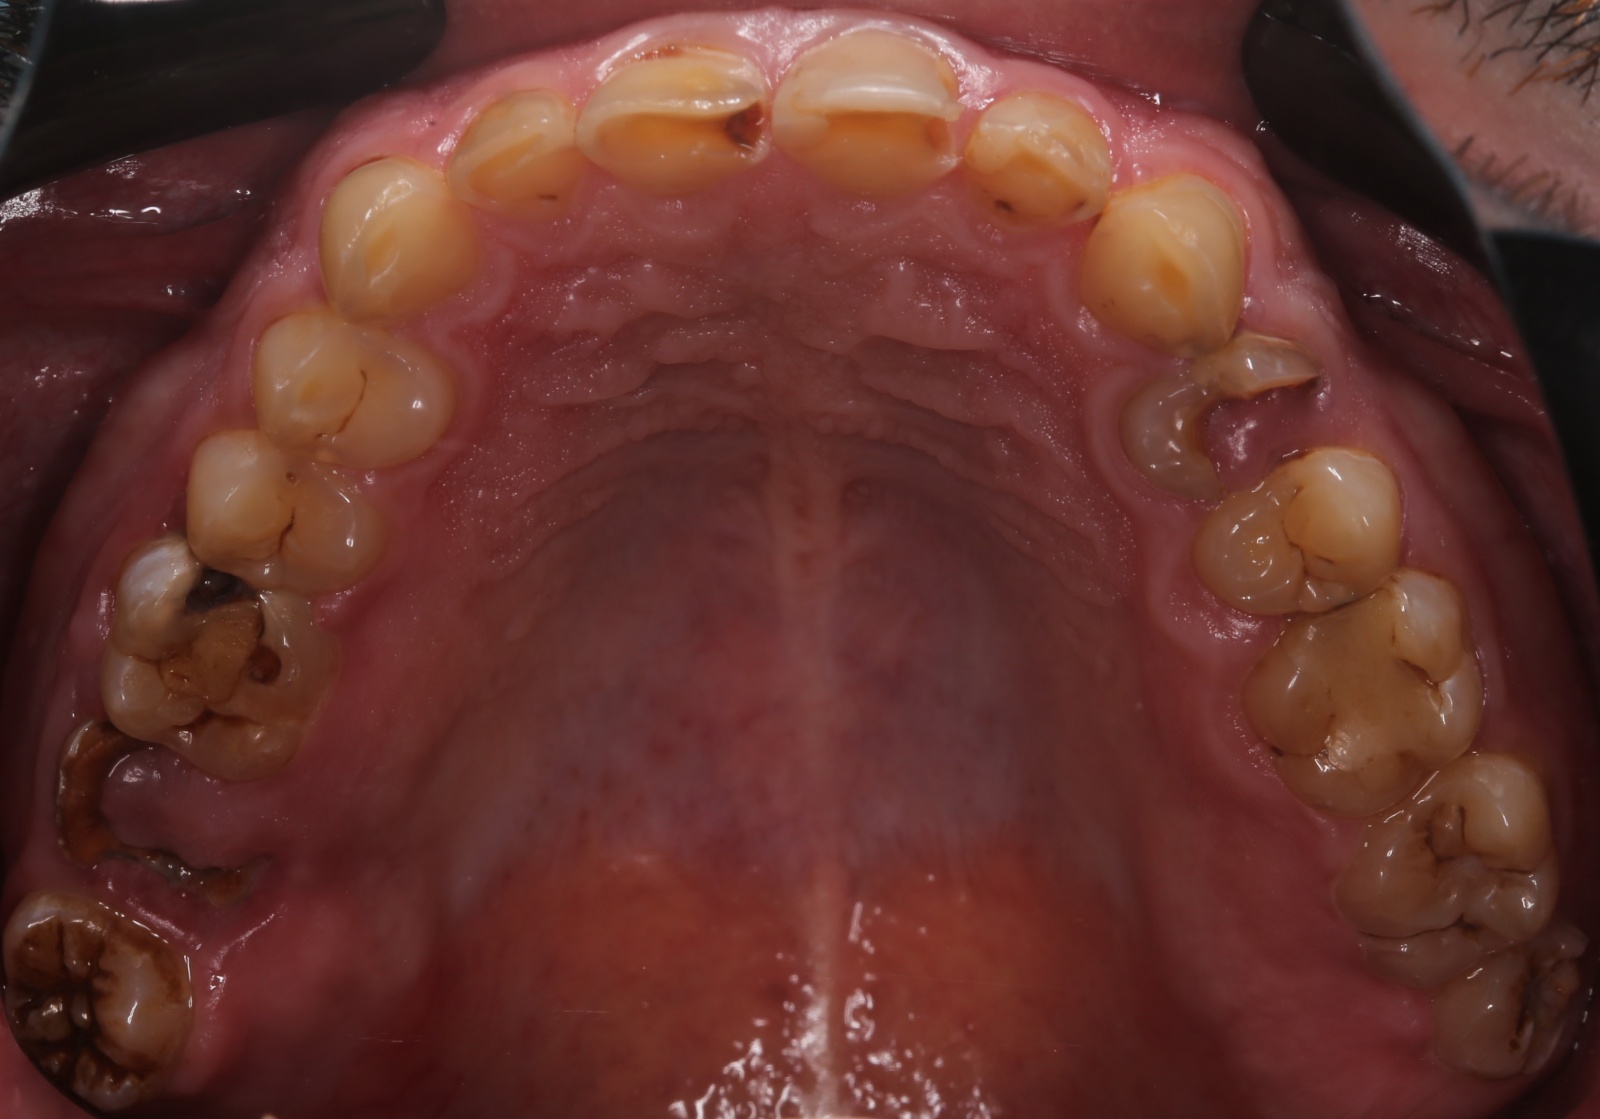

Напоминаю: он пришёл к нам вот в таком состоянии:

На нижней челюсти у него жевательных зубов не было вообще:

С верхней было немного получше, но не так чтобы сильно:

Жалобы были не только на внешний вид зубов, но ещё и на проблемы с дыханием и приёмом пищи. Общаться с людьми было тоже некомфортно.

В жевательном отделе зубов практически нет. На зубах с первого по пятый появились небольшие фасетки стираний, которые означают, что прикус зафиксирован именно на них. Если они настолько отчётливые, как у Ивана, это значит, что зубы начинают стираться, и высота нижнего отдела лица уменьшается. Значит, придётся повышать прикус, чтобы вернуть височно-нижнечелюстной сустав и зубы в первоначальную здоровую позицию. Это будет моей задачей.

Смотрим дальше.

Такие разрушенные зубы, заросшие десной, кричат о необходимости имплантации

Кариозные процессы сигналят о терапевтической реабилитации и терапевтической санации полости рта

Воспалённые дёсны намекают на пародонтологию